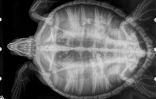

Les agents de la Réserve Marine ont récupéré une tortue imbriquée affaiblie, il y a une quinzaine de jours du coté du sentier sous-marin de l'Ermitage. "La tortue a été prise en charge par le Centre de soins de Kélonia pour un certain nombre de contrôles. La prise de sang et la radio de la tortue montrent des problèmes intestinaux sans gravité qui ont pu être traités rapidement. La tortue va donc pouvoir rejoindre le lagon ce vendredi 3 février matin" précise le centre de soins Kélonia.